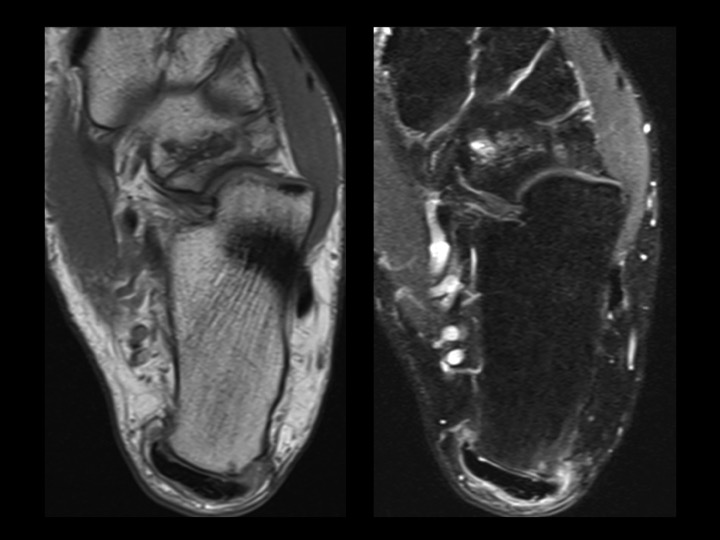

Although there have only been 9 cases of navicular-cuboid coalition reported up to 2012 (up to and including the reference for case #1390), here is another case in a 30M with bilateral non-osseous navicular-cuboid coalition (white arrows; changes more pronounced on the left). He has left-sided Haglunds deformity, which relates to his symptoms. Although the 4 cases reported in the reference from #1390 had midfoot pain, I am struck that this patient, and the 10 yr old from #1390 both present with hindfoot pain. I imagine the midfoot tarsal coalition might have a global impact on foot biomechanics.

navicular-cuboid coalition